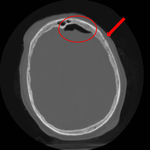

Axial CT scan demonstrating an open nondepressed linear skull fracture (arrow) associated with pneumocephalus (circle)

From the teaching collection of Demetrios Demetriades; used with permission